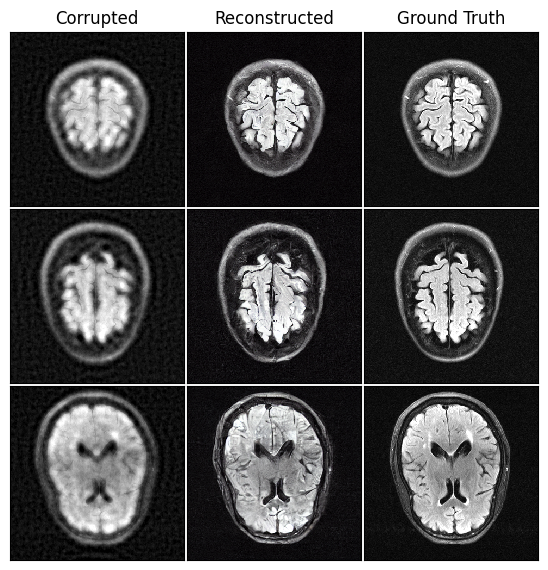

In this section, we provide additional empirical results on high-resolution satellite (256 x 256) and MRI datasets (320 x 320) corrupted by Poisson noise and compressive sensing (CS). For MRI, the experiments are conducted in the latent space for computational efficiency. The results remain consistent with those in the main text, further validating the effectiveness of SFBD-OMNI across diverse corruption settings. At the same time, qualitative inspection reveals visible reconstruction artifacts, indicating remaining limitations and motivating future work that incorporates stronger priors or modality-specific inductive biases.

MRI image set and compressive sensing corruption. We conduct our experiments on the fastMRI brain dataset (ZbontarKSMHMDS2018), using its multicoil training subset, which provides fully sampled raw -space data from clinical brain MRI scans. For each volume, we discard the final four slices, as these typically contain little or no brain anatomy. After filtering, the dataset contains 52,778 MRI slices, from which we randomly sample 2,000 as the clean set.

For this dataset, we consider the compressive sensing degradation, which is a natural corruption model for MRI. In particular, MRI scanners do not acquire images directly; instead, they measure the spatial frequencies of the underlying anatomy in -space (LustigDP2007). The acquisition process therefore corresponds to sampling the Fourier transform of the image. Because clinical MRI protocols routinely undersample -space to shorten scan time, compressed-sensing MRI accelerates acquisition by collecting only a subset of frequency coefficients and relying on reconstruction algorithms to recover the missing data. Consequently, partial Fourier undersampling is not an artificial degradation, but a realistic and practically motivated corruption process for accelerated MRI.

To simulate a realistic compressive sensing degradation, we follow the standard undersampled MRI acquisition model of LustigDP2007. Given an image , the corrupted observation is obtained by undersampling its Fourier transform:

where denotes the 2-D discrete Fourier transform and is a binary mask selecting a subset of frequency coefficients. We use a fixed variable-density sampling mask, generated once at the beginning of the experiment and reused for all samples. Following common practice in compressed-sensing MRI, the central low-frequency region of -space (10% of the spatial extent) is fully sampled to preserve global structure, while coefficients outside this region are sampled independently with probability . This produces a realistic and reproducible compressive sensing corruption operator that retains essential low-frequency content while heavily undersampling high-frequency components.

Results. Table 5 summarizes the FID performance of online SFBD-OMNI for satellite images with Poisson corruption and MRI scans under compressive sensing, measured after pretraining and after online iterative refinement. Across all evaluated settings, the online phase yields a clear improvement over the pretrained model, demonstrating the effectiveness of SFBD-OMNI as a general reconstruction framework for real-world corruption processes.

We provide qualitative reconstructions in Figures 5 and 6. On satellite images, SFBD-OMNI visibly recovers large-scale structures – such as building layouts, runway geometry, and aircraft outlines – that are heavily disrupted by Poisson shot noise. In the MRI setting, despite severe undersampling, the method reconstructs coherent tissue boundaries and globally consistent anatomical structure.

Limitations and noise sensitivity. While our framework produces promising reconstructions, the Poisson-noise results also reveal a clear limitation. As the photon budget decreases (i.e., noise increases), output quality degrades, with more residual artifacts and reduced fine-grained fidelity. This trend is reflected quantitatively in Table 5, where performance drops moving from to . Qualitative examples in Figure 5 further highlight these failure modes–under extreme shot noise, texture-level restoration remains challenging and fine structure is only partially recovered. Likewise, for MRI samples corrupted by compressive sensing, we still notice some visible artifacts as shown in Figure 6.

Across both Poisson-corrupted satellite imagery and compressive-sensed MRI scans, SFBD-OMNI reliably recovers the global structure of the underlying data distribution, but struggles to reconstruct fine details, particularly under severe corruption. Poisson noise reduces the amount of usable information in low-photon settings, and similarly, heavy MRI undersampling restricts the available signal for reconstruction. In such cases, recovering the clean distribution becomes inherently more challenging and may require stronger priors or model-specific inductive biases.